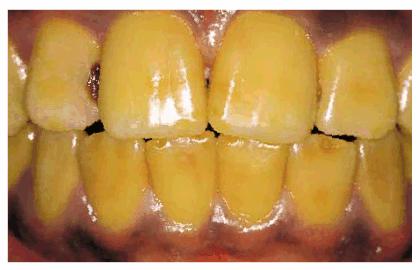

Figure 16-2A and B: Total neglect resulted in severe staining

of this patient's teeth.